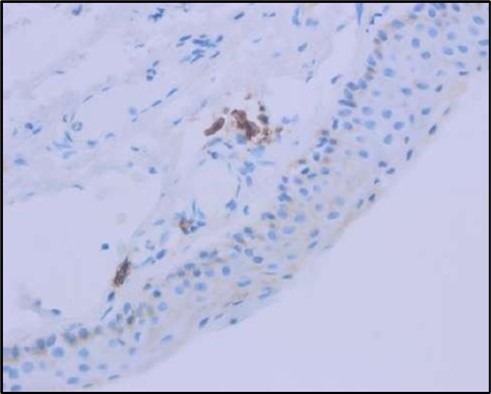

Two weeks post-surgery, the left eye showed significant healing, with a small conjunctival granuloma and vascularization at the ulcer margins. The cornea was clear with a central leading edge nasally, deep and quiet anterior chamber and clear lens. VA 6/6 bilaterally and IOP normal. Histopathology of excised conjunctiva showed non-keratinized squamous epithelium with superficial erosions, stromal elastosis, hemorrhage, and inflammatory infiltration, but no signs of granulomatous disease, malignancy, or viral evidence, findings consistent with idiopathic localized inflammatory process. The patient reported significant relief and satisfaction post-surgery, resuming normal activities. Treatment continued with oral prednisolone 25 milligrams every other day, tobramycin-dexamethasone ointment twice daily, and preservative-free artificial tears four times daily Figure 4, Figure 5a, Figure 5b, Figure 5c, Figure 5d.

Figure 5c.OS, Immunohistochemical stain using CD45 (leukocyte common antigen) demonstrating a dense population of lymphocytes stained brown

Figure 5d.OS, Immunohistochemistry using CD138 showing many plasma cells (brown-stained) in the inflamed tissue.

Histopathological examination revealed a dense infiltration of CD138-positive plasma cells within the excised conjunctival tissue (Figure 5b, Figure 5c, Figure 5d). This finding supports an antibody-mediated immunopathogenesis in Mooren’s ulcer, consistent with Type II and Type III hypersensitivity mechanisms described in the literature 20, 21. The prominent presence of CD138- positive plasma cells provide a clear pathological rationale for conjunctival resection, as excision of the immunologically active perilimbal conjunctiva effectively removes the local 'factory' of autoantibodies that drive corneal stromal destruction, thereby halting ongoing tissue damage 21.